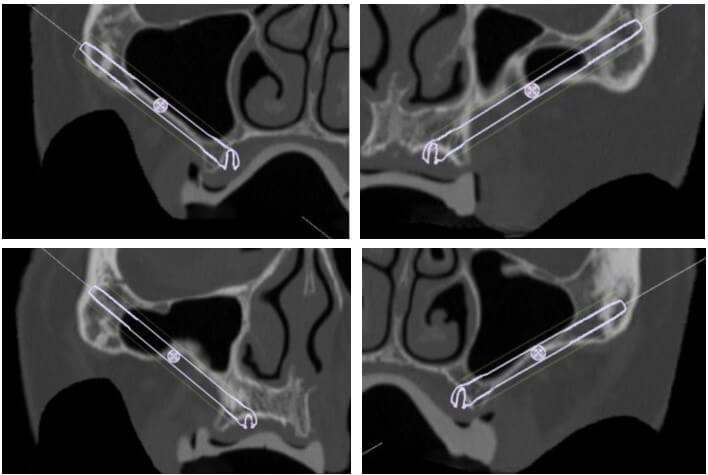

Realizamos CT helicoidal y con FOV ampliado, imprescindible para el diseño de las guías.

Planificamos cuidadosamente la colocación de los implantes teniendo en cuenta, tanto la anatomía maxilofacial como la de la futura prótesis

Planificación 3D personalizada

Planificación 3D y confección de férulas quirúrgicas para abordaje guiado.